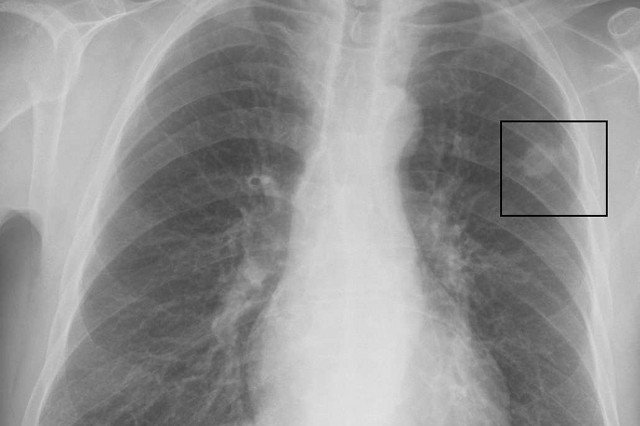

W Pekinie szybko wzrasta liczba pacjentów z nowotworem płuc. Tylko w 2011 roku zarejestrowano tam 7 999 nowych przypadków tej choroby (63 chorych na 100 000 mieszkańców). Tymczasem zaledwie dekadę wcześniej statystyki były wyraźnie lepsze (40/100 000). Za wzrost liczby zachorowań może odpowiadać coraz bardziej zanieczyszczone powietrze.

O wzroście liczby zachorowań na nowotwory płuc poinformowała państwowa Agencja Informacyjna Xinhua. Z oficjalnych danych wynika, że od 2002 roku systematycznie przybywa pacjentów, u których zdiagnozowano tę chorobę. W ciągu 2011 roku w samym tylko Pekinie zarejestrowano 7 999 nowych przypadków nowotworu płuc. Stanowiły one 20,8 procent wszystkich odnotowanych w tamtym roku przypadków nowotworów złośliwych. Rak płuc był najczęściej występującym rodzajem nowotworu wśród mężczyzn cierpiących na nowotwór złośliwy.